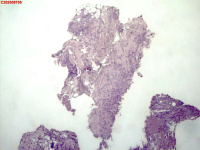

| 图片: | |

- 右侧胸壁穿刺组织活检

| 性别 | 女 | 年龄 | 81岁 | 临床诊断 | 胸锁关节结核? |

| 一般病史 | 胸部CT示:右肺下叶小结节,建议3-6个月复查,必要时胸外科会诊。左肺上叶多发小斑点、结节影,结核可能。右肺上叶多发点状影。双肺间质性改变。纵隔淋巴结肿大、钙化。右侧胸锁关节见骨质破坏,周围见软组织肿胀。 | ||||

| 标本名称 | 右侧胸壁穿刺组织活检 | ||||

| 大体所见 | B超:体表包块彩超示右侧胸壁混合回声包块,右侧胸壁低回声区,CDFI示:其内未见明显血流信号。 | ||||